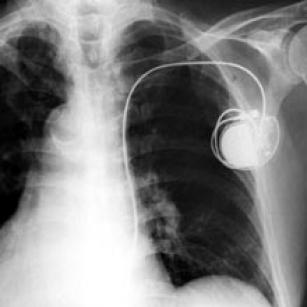

Common pacemaker problems (part 4)—troubleshooting 21st Sep 2015 - Kristian Webb Today's lesson is called "Common pacemaker problems and resolutions". In it you will learn how you can use and adjust ...

Common pacemaker problems (part 3): Oversensing 18th Sep 2015 - Kristian Webb Oversensing can be a life-threatening event. Especially in your patients who are pacemaker dependent. So it’s ...

Common pacemaker problems (part 2)—undersensing 16th Sep 2015 - Kristian Webb Undersensing can be a life-threatening problem in our pacemaker patients. It’s important that you recognize it when ...

Common pacemaker problems (part 1)—failure to capture 14th Sep 2015 - Franz Wiesbauer, MD, MPH In today’s teaching video, pacemaker expert Kristian Webb from the UK will explain why it’s important that you know ...